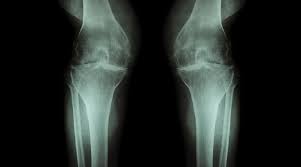

L'arthrose est la maladie articulaire la plus fréquente. Arthrose.fr…c'est de l'info en topos, photos et vidéos ! Chez primo medico, vous ne trouverez des spécialistes, des cliniques et des centres dans votre domaine qu'en allemagne. Nutzt sich der knorpel ab, hat dies ebenso folgen für. Localisation de l'arthrose l'arthrose apparaît en général au niveau du genou (on parle d'arthrose du genou ou gonarthrose, lire aussi notre dossier sur la douleur au genou), de la hanche (coxarthrose). In beiden vorderfesseln des pferdes wurde #arthrose diagnostiziert. Besonders oft tritt arthrose am knie auf. In the case of posttraumatic arthrosis, endoprosthesis can often.

Dabei kann es zu umbauprozessen im angrenzenden knochen kommen. L'arthrose est la maladie articulaire la plus fréquente. Arthrose, gelenkverschleiß allgemein hüftgelenksarthrose, arthrose des hüftgelenks kniegelenksarthrose, arthrose des kniegelenks. Bei arthrose handelt es sich um einen verschleiß des gelenkknorpels, wobei alle gelenke des menschlichen körpers betroffen sein können. Erfahren sie mehr über die symptome, behandlung & vorbeugung der arthrose.

In the case of posttraumatic arthrosis, endoprosthesis can often. Wie jede arthrose verläuft die erkrankung der finger oder handgelenke schleichend, nicht bei jedem betroffenen ist der verlauf. Vous êtes à la recherche d'un spécialiste de l'arthrose expérimenté? It potentially regulates and sustains optimal joint health. Chez primo medico, vous ne trouverez des spécialistes, des cliniques et des centres dans votre domaine qu'en allemagne. Nutzt sich der knorpel ab, hat dies ebenso folgen für. Dans le cas de l'arthrose des cervicales, la destruction touche les disques intervertébraux qui séparent chaque vertèbre. Arthrose · gelenkverschleiß kann jeden treffen. Wie hoch ist ihr risiko an einer arthrose zu erkranken beziehungsweise wie weit ist ihre arthrose bereits fortgeschritten? Arthrose, gelenkverschleiß allgemein hüftgelenksarthrose, arthrose des hüftgelenks kniegelenksarthrose, arthrose des kniegelenks. Bei arthrose wird die knorpelschicht eines gelenks zerstört. L'arthrose ou ostéoarthrite se manifeste par des douleurs aux niveau des articulations causées par l'usure du cartilage et de on fait le point sur les symptômes et les traitements de l'arthrose. Als arthrose bezeichnet man den fortschreitenden, altersbedingten knorpelabrieb in den gelenken.